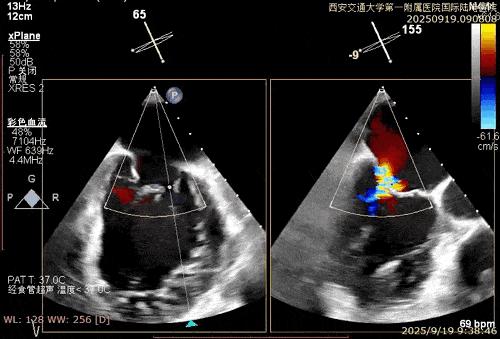

术中在超声引导下完成房间隔穿刺,将第一枚XTR在左房内完成终定位,2偏3区完成植入,夹合效果良好,即刻超声显示轻微反流,完成夹子释放,手术效果良好,手术圆满结束,患者术后6小时即实现床旁活动。